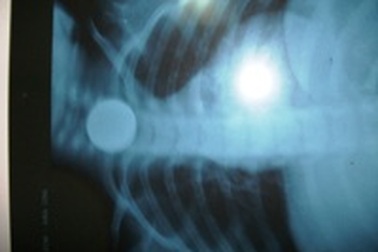

Cứu sống cháu bé 3 tuổi nuốt đồng tiền xuChiều ngày 5/11, tin từ Bệnh viện Hữu Nghị Việt Nam – Cuba Đồng Hới cho biết, khoa cấp cứu bệnh viện này vừa cứu sống một cháu bé 3 tuổi, nuốt đồng tiền xu.